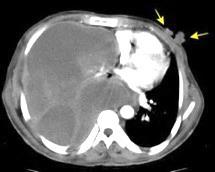

10-20% de pacientes las larvas alcanzan la circulación sistémica y pueden llegar a cualquier órgano También pueden llegar a órganos intrabdominales por migración transmural.

Yagmur Y et al. Unusual Location of Hydatid Cysts: A Case Report and Literature Review. Int Surg. 2012 / Pedrosa I et al. Hydatid disease: radiologic and pathologic features and complications . Radiographics 2000.